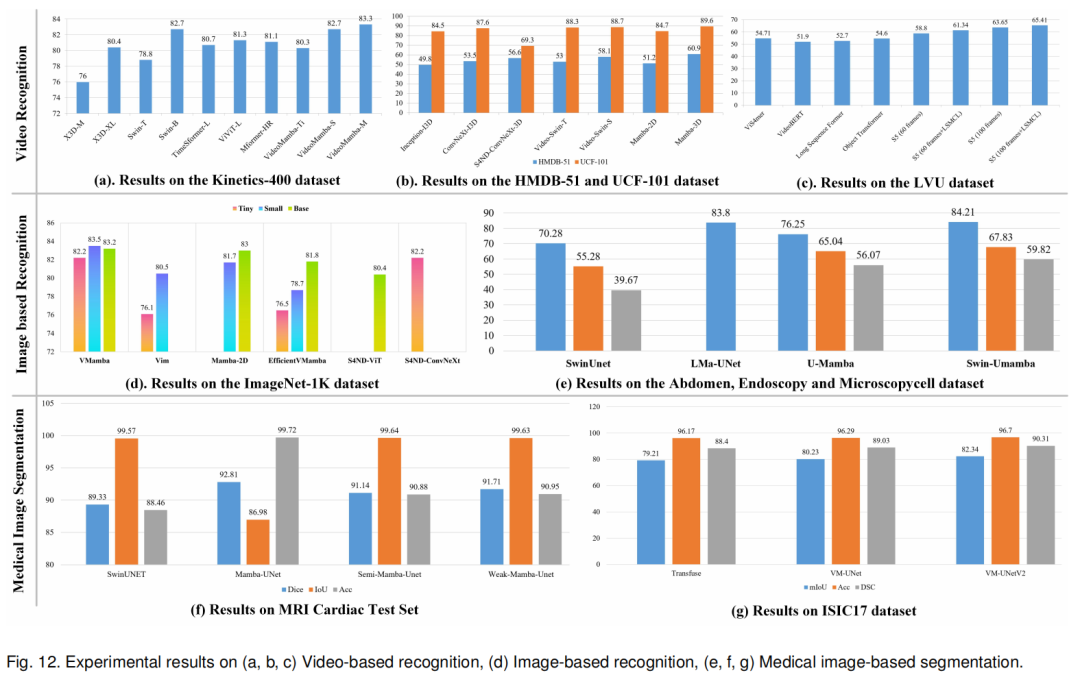

1)单/多标签分类(Single-/Multi-label Classification)

2)视觉目标跟踪(Visual Object Tracking)

3)文本到图像的生成(Image-to-Text Generation)

4)行人/车辆重识别(Person/Vehicle Re-Identification)